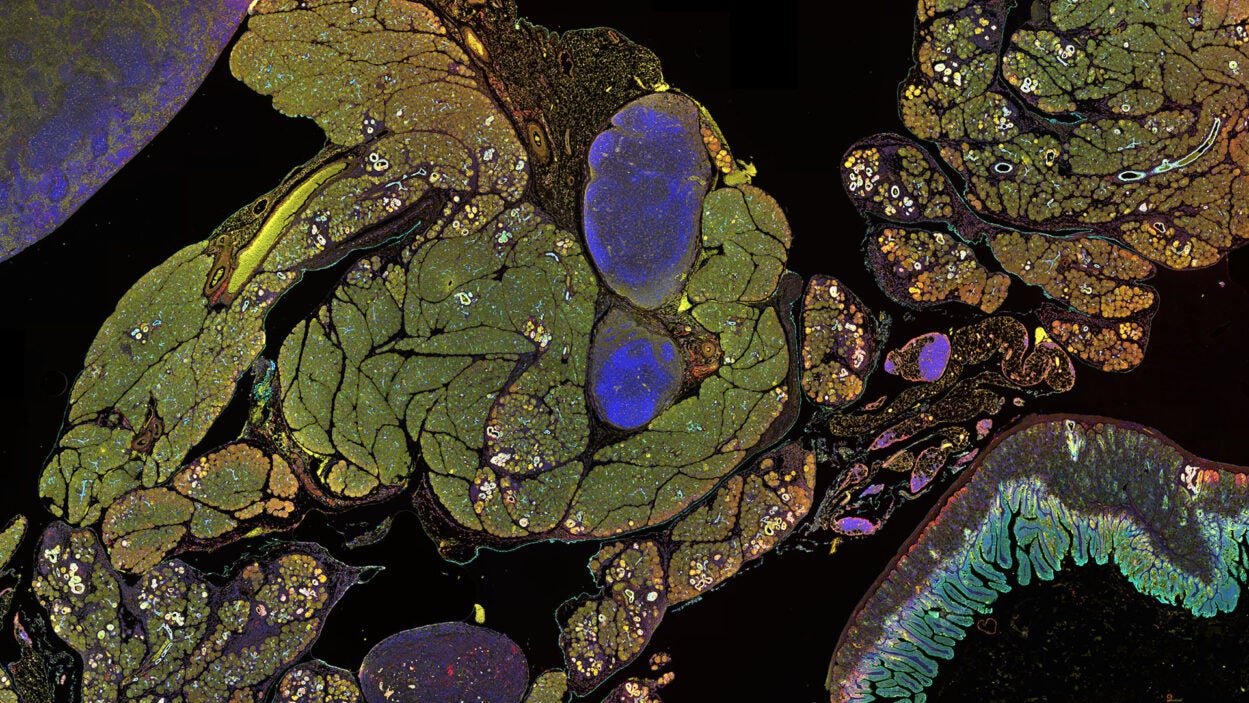

Feature

An angry peacock is no joke. Like the colorful bird and its tall tail feathers, cancer biology can make for some eye-catching images. Read the story »

Feature

That’s not the Starship Enterprise burning up in space. It’s an up-close look at precancerous pancreatic lesions and the mucus they produce. Read the story »